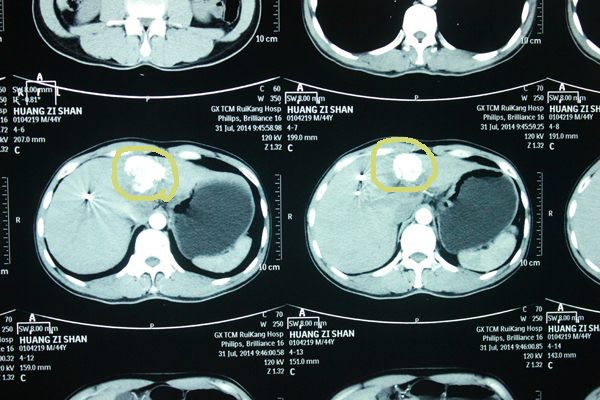

7月31日,在射波刀治疗一个月后黄先生再次来到医院复查,经查他的肿瘤得到有效控制,并未扩散到健康肝脏组织及其他器官。

射波刀后肿瘤明显缩小